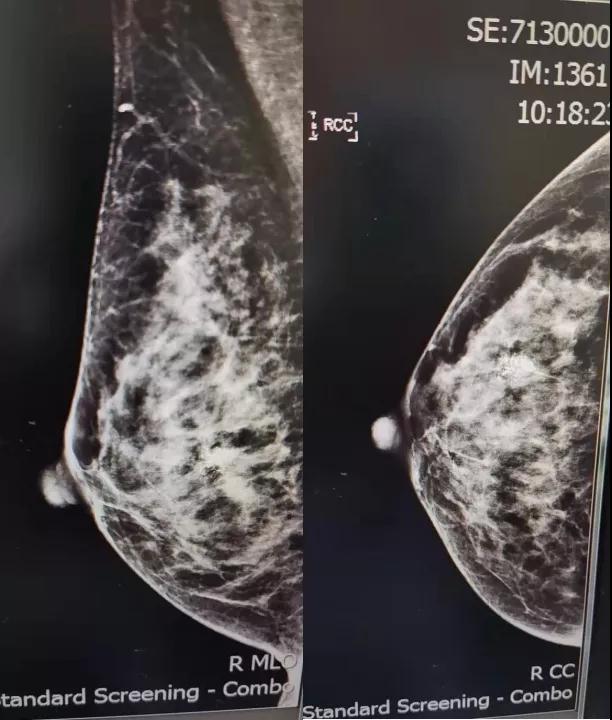

B超:右侧乳腺低回声区,大小约2. 3x1. 3cm(BI-RADS:4b类,提示:乳腺Ca不除外;

钼靶:右乳成簇钙化考虑恶性 [B1-RADS:4C类]。

CT示:右乳病变,提示乳癌可能,肝右叶散在钙化灶。余肝内散在小结节,考虑肝囊肿。右肾结节,考虑肾囊肿。

MRI示: 右乳外下象限腺体边缘处肿块,考虑:乳腺癌。各项检查腋窝淋巴结均(-)。患者个人史、既往史、肿瘤家族史均无特殊。

术前钼靶